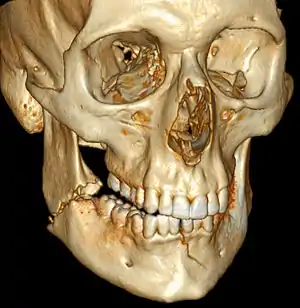

![]() | |

| 3D computed tomographic image of a mandible fracture in two places. One is a displaced right angle fracture and the other is a left parasymphyseal fracture. | |